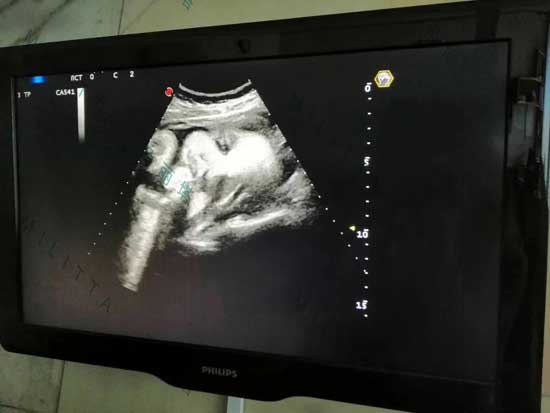

在这位开朗的代母在医院体检完后,我们邀请她到办公室,跟自己怀上孩子有重大联系的中国客户视频,非常期待宝宝出生后双方的第一次碰面~~